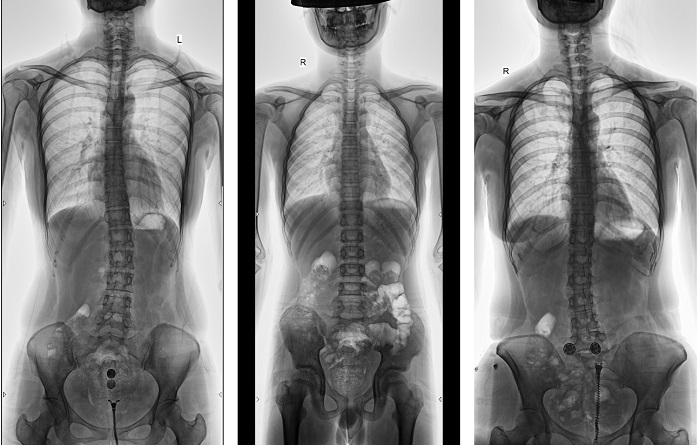

動(dòng)態(tài)DR全景拼接功能突破平板尺寸長(zhǎng)度限制,可進(jìn)行立臥位攝影,對(duì)脊柱、下肢及下肢靜脈造影進(jìn)行分段攝片,然后對(duì)分段圖像進(jìn)行拼接,在一幅X光圖像上完整顯示全脊柱或下肢整體形態(tài),獲得全脊柱或全下肢圖像,有效解決了傳統(tǒng)X光片不能一次成像問題,通過直觀顯示脊柱和下肢的整體解剖形態(tài)及側(cè)凸部位,為臨床治療提供重要參考依據(jù)。

▲全脊柱DR影像

普利德多功能動(dòng)態(tài)DR進(jìn)行全脊柱全下肢圖像拼接時(shí),影像密度均勻、清晰、接緣處過渡自然,圖像質(zhì)量高,完全能滿足臨床觀察、診斷及測(cè)量要求。拍片過程也更加方便快捷,使患者得到快速診斷,及時(shí)治療,為臨床醫(yī)生和患者帶來更大的便利,大大助力醫(yī)院醫(yī)療服務(wù)能力的提升!